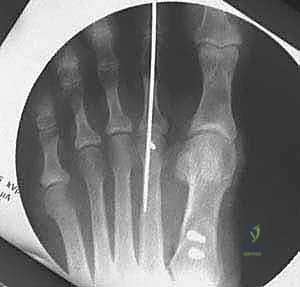

- التصوير بالأشعة السينية (X-rays) أثناء الوقوف: هذا أمر بالغ الأهمية. الأشعة والوزن محمل على القدم تظهر الدرجة الحقيقية للتشوه.

يقوم الدكتور هطيف بقياس زوايا محددة:

* زاوية إبهام القدم الأروح (HVA): الزاوية بين عظم المشط الأول والإصبع الكبير.

* الزاوية بين الأمشاط (IMA): الزاوية بين عظم المشط الأول والثاني.

بناءً على هذه الزوايا، يتم تصنيف الحالة إلى خفيفة، متوسطة، أو شديدة. جراحة (ماو) تُخصص عادة للحالات المتوسطة إلى الشديدة التي تتطلب تصحيحاً كبيراً ومستقراً.